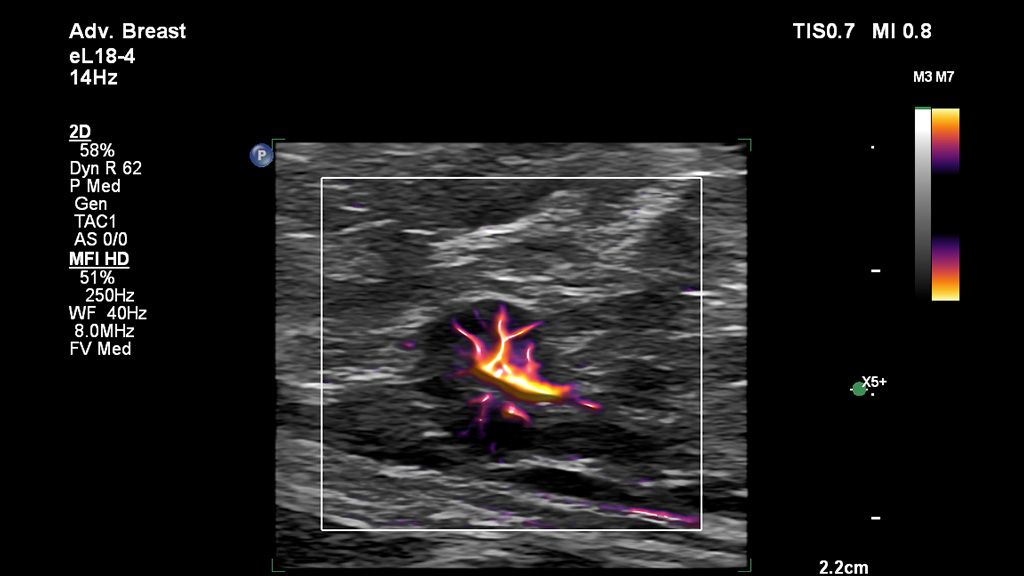

• Breast Flow Viewer

Flow Viewer represents vascular flow topography with a 3D-like appearance and MicroFlow Imaging is designed to detect and assess blood flow anatomy in tissue.

• MicroFlow Imaging HD detects small vessel blood flow with twice the sensitivity and resolution of MicroFlow.3